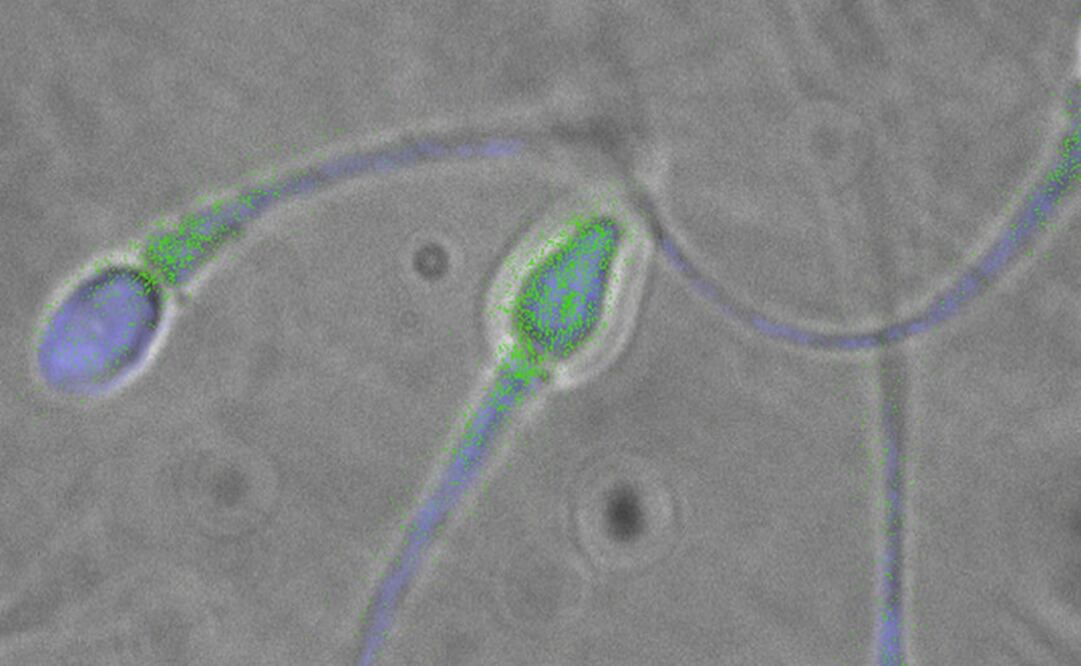

Los investigadores también encontraron 11 especies de virus en los testículos, lo que sugiere que estos sitios del cuerpo humano les permiten a dichos microorganismos sobrevivir más tiempo de lo que sucede en la sangre.

Esto es así porque el sistema inmunitario "busca" combatir primero a los patógenos localizados en la sangre y, en cambio, el semen se presenta como un escondite estratégico.